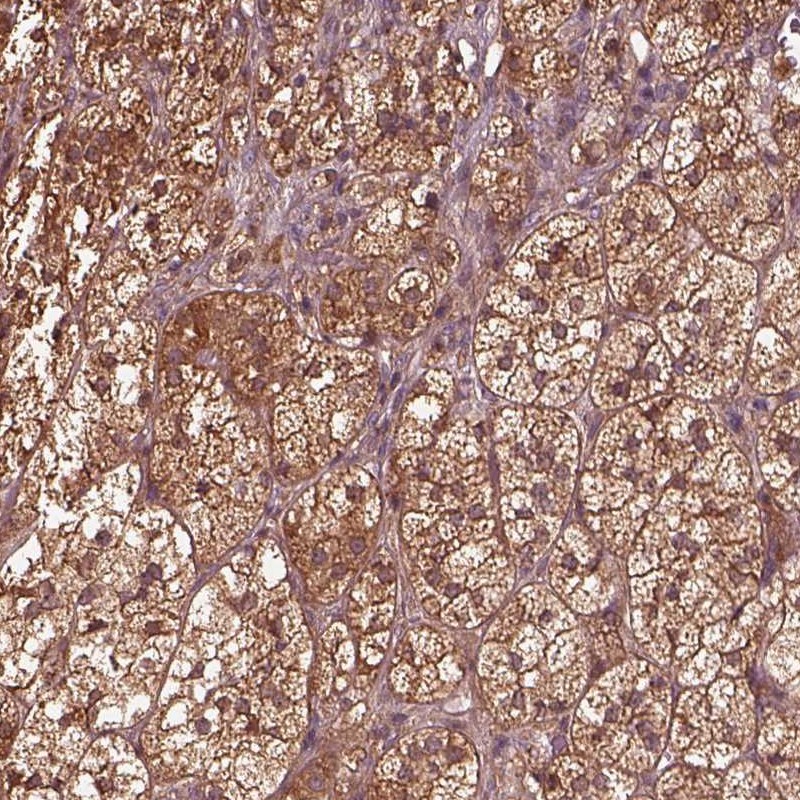

Immunohistochemical staining of human adrenal gland shows strong cytoplasmic positivity in glandular cells.